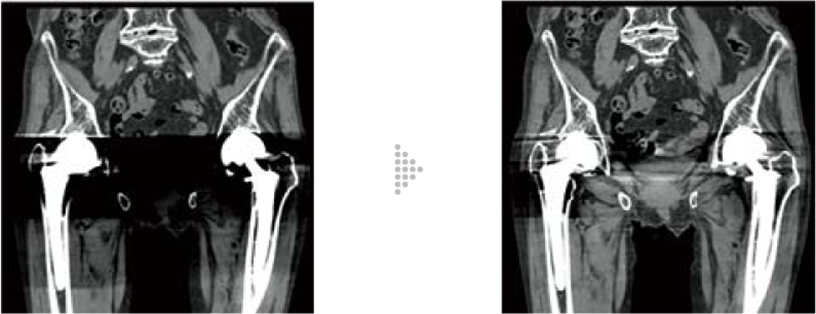

This technology reduces metal artifacts by applying iterative processing. Metallic parts are extracted to estimate the artifacts for correction. The effect level can be selected to meet your purpose.

FBP(Left)

HiMAR Plus(Right)